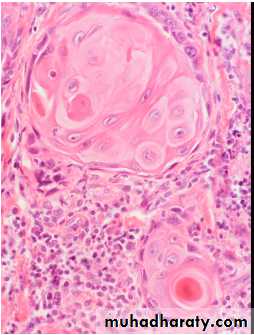

The pink cytoplasm with distinct cell borders and keratin pearls characteristic for a squamous cell carcinoma

Pathologically, it distinguished from other NSCLCs by the presence of keratinization, pearl formation, and intercellular bridging.